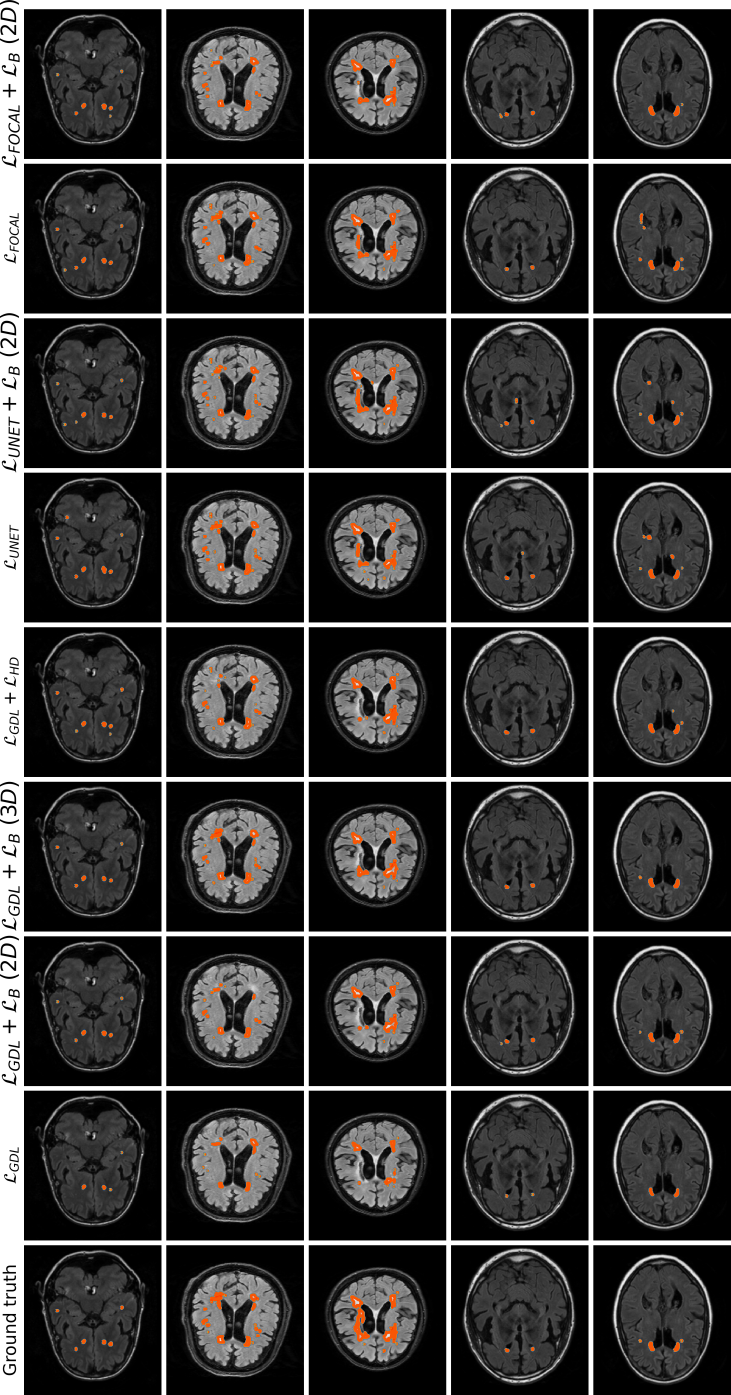

Qualitative evaluation

Qualitative results are depicted in Fig. 4. Inspecting these results visually, we can observe that there are two major types of improvements when employing the proposed boundary loss. First, as the methods based on DSC losses, such as GDL, do not use spatial information, prediction errors are treated equally. This means that the errors for pixels/voxels in an already detected object have the same importance as the errors produced in completely missed objects. On the contrary, as our boundary loss is based on the distance map from the ground-truth boundary , it will penalize much more such cases, helping to recover small and far regions. This effect is best illustrated in Fig. 1 and Fig. 4 (third row). False positives (first row in Fig. 4) will be far away from the closest foreground, getting a much higher penalty than with the GDL alone. This helps in reducing the number of false positives. Additional qualitative results for other base losses, and their combination with the proposed boundary loss, are depicted in Figures 5, 6. These figures also show failure cases (last column) of the boundary loss.